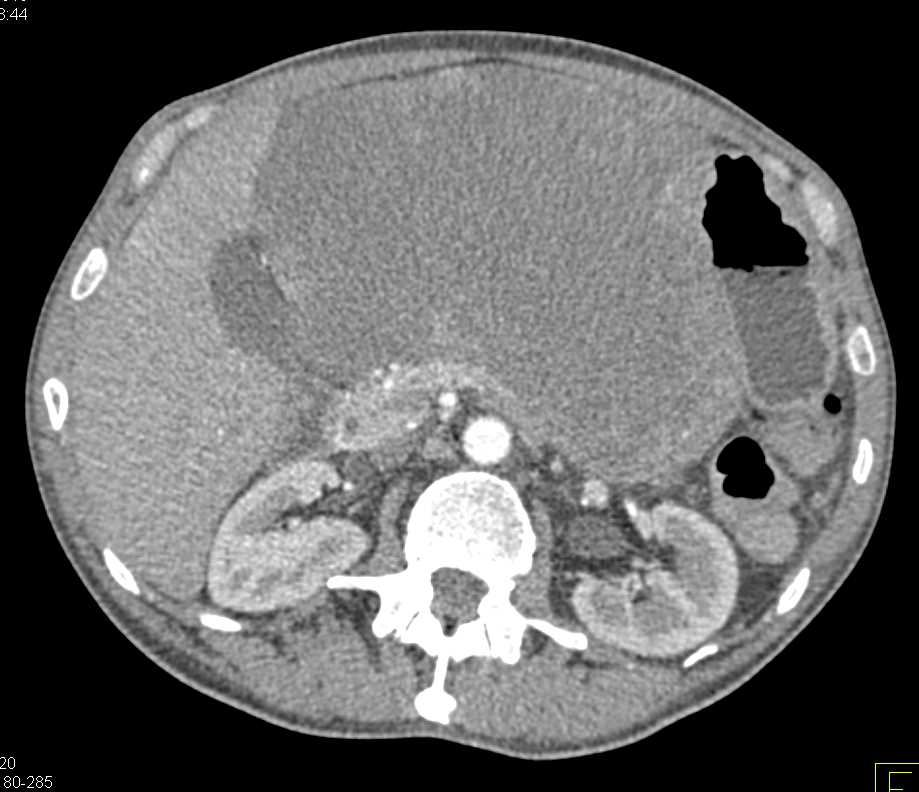

Lagre Gastric GIST Tumor